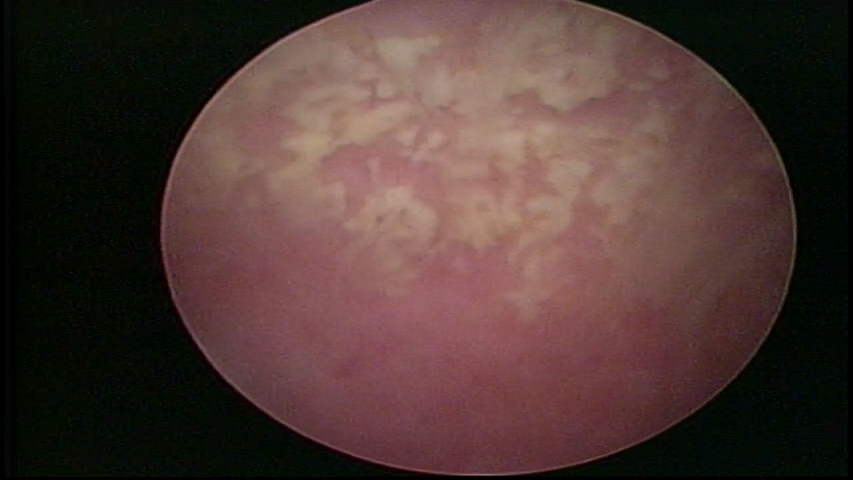

ENDOMETRITE CRÔNICA

Já na Endometrite crônica avançada visualiza-se um endométrio delgado, com áreas desnudas, às vezes, ulcerada, com uma coloração cinza esverdeada com micro varizes, de coloração mais acastanhada, mais acentuada nas regiões cornuais (distrofia vascular).